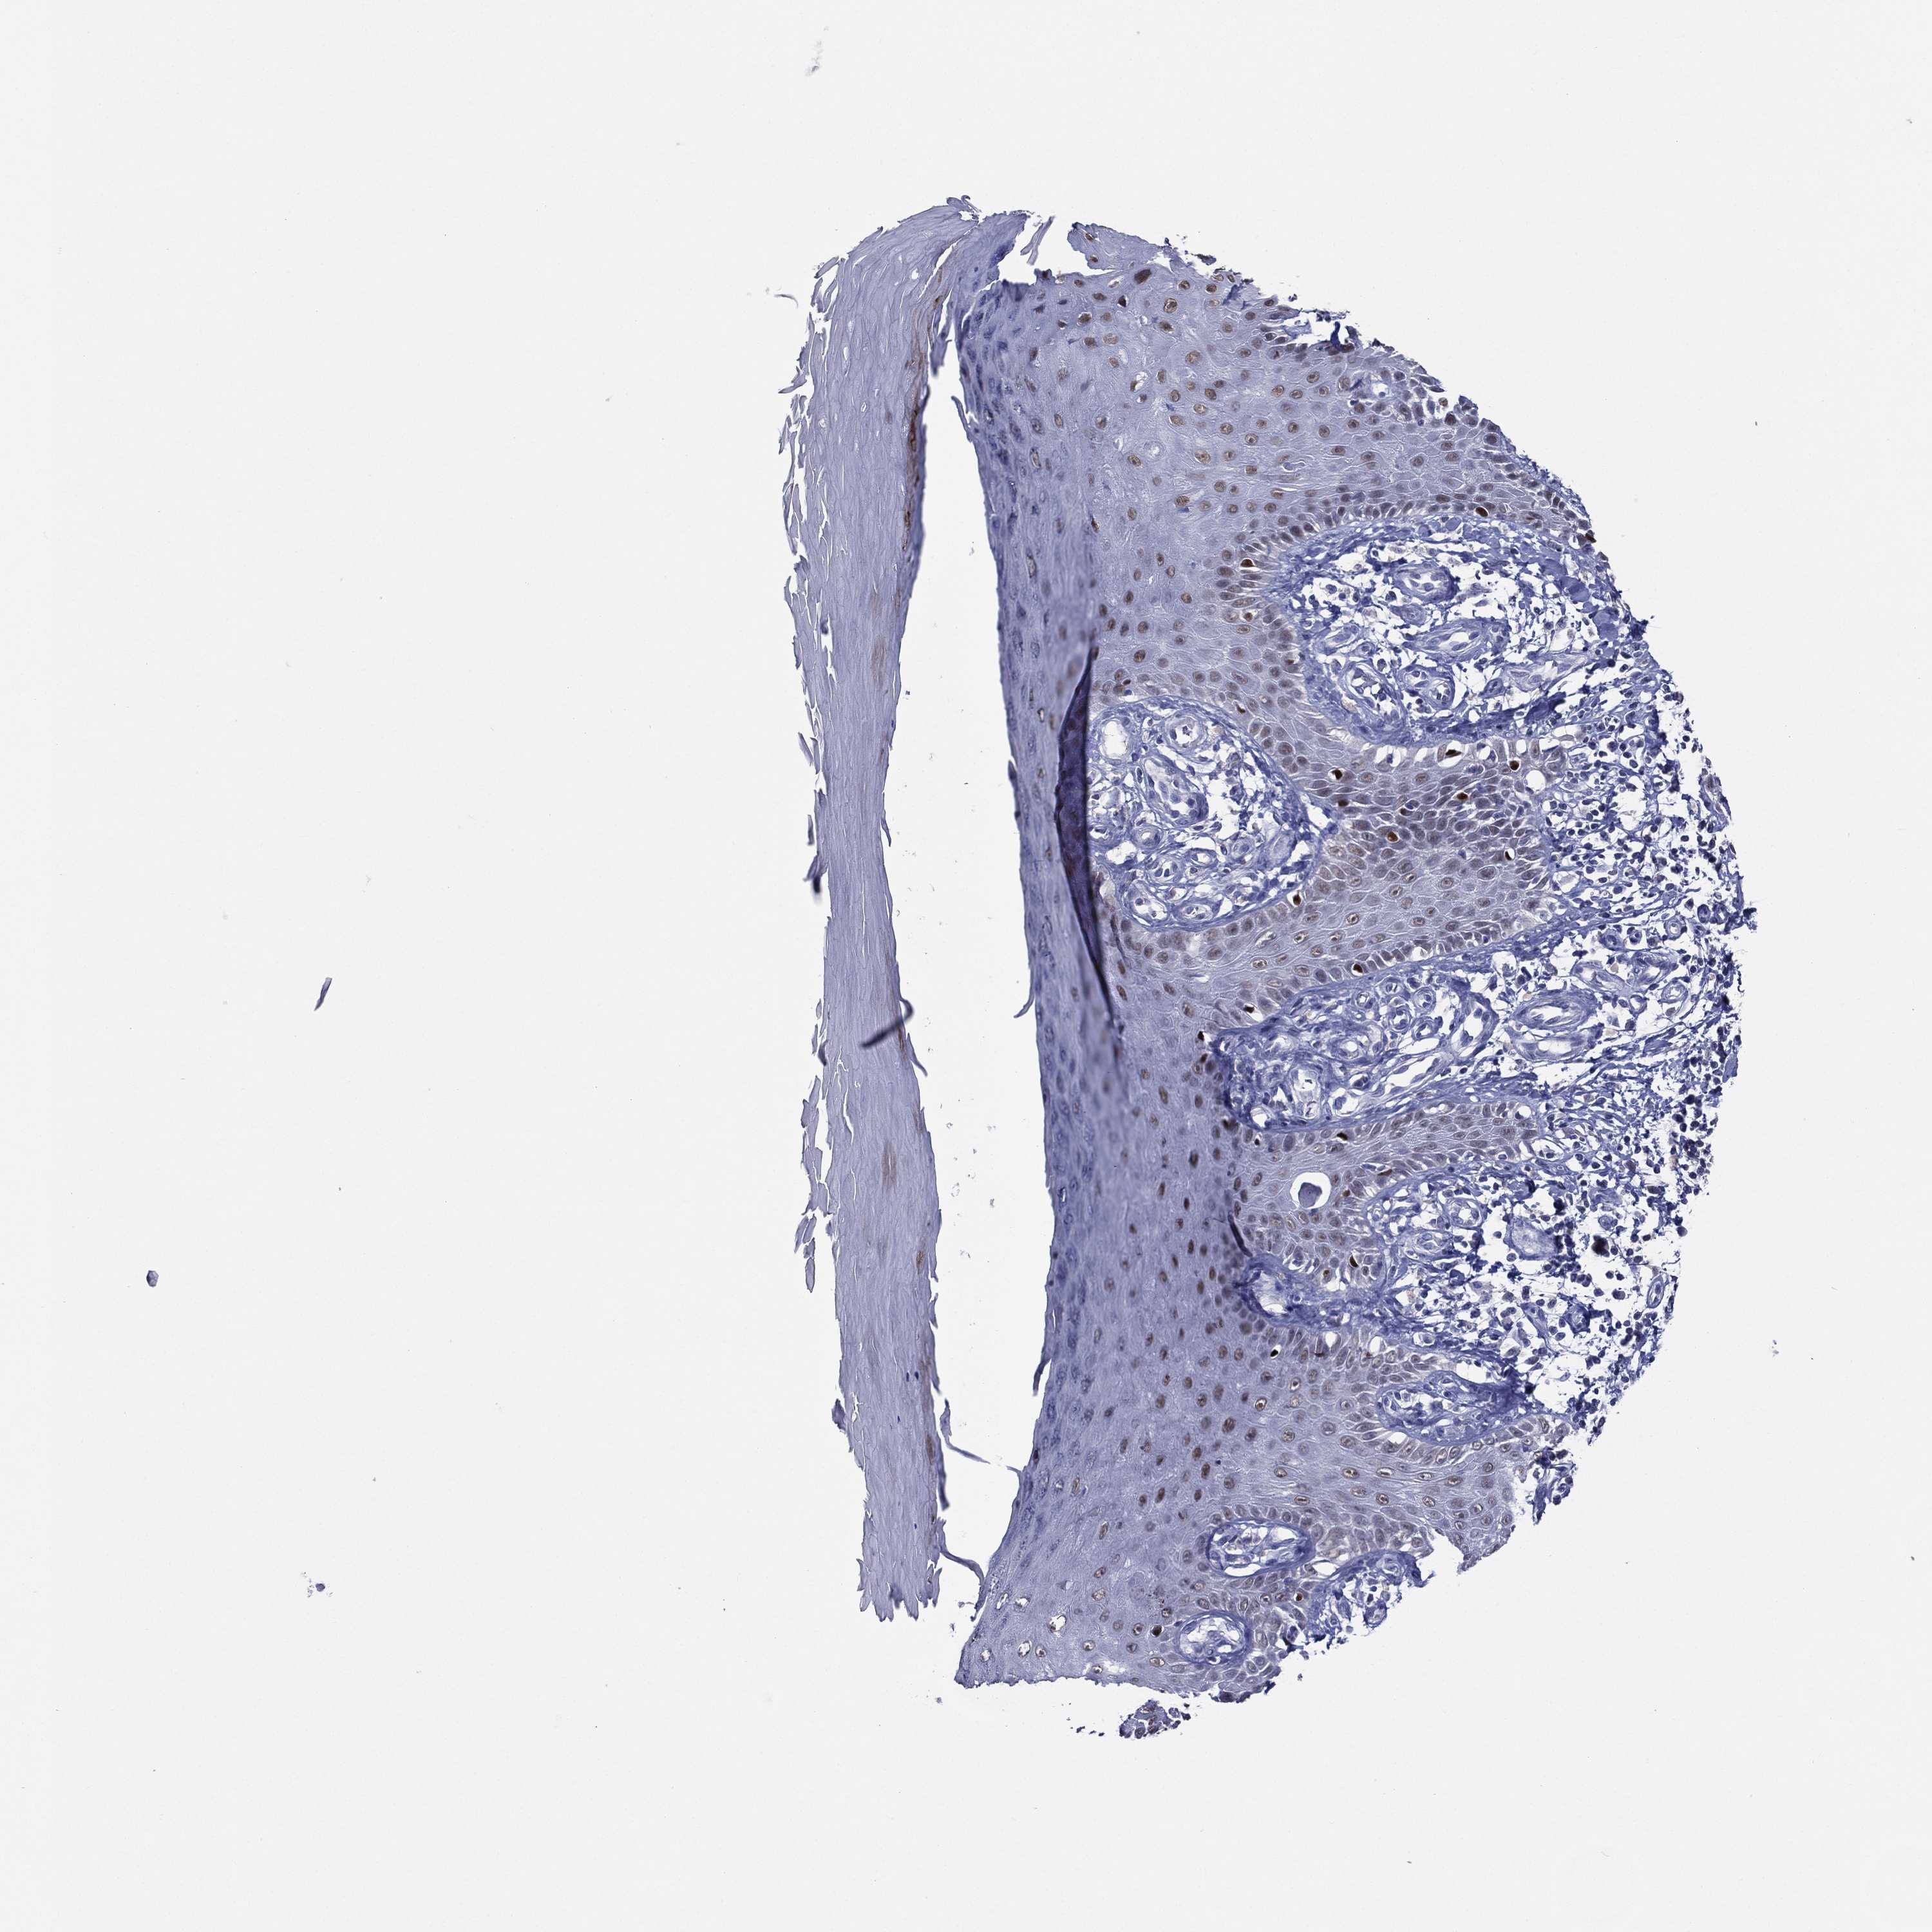

SKIN 2 - Antibody stainingi

Antibody staining in the annotated cell types in the current human tissue is reported as not detected, low, medium, or high, based on conventional immunohistochemistry profiling in selected tissues. This score is based on the combination of the staining intensity and fraction of stained cells.

Each image is clickable and will lead to virtual microscopy that enables deeper exploration of all samples and also displays staining intensity scores, fraction scores and subcellular localization as well as patient and tissue information for each sample.

Antibody HPA056871Antibody CAB000326

Cells in basal layer -Medium

Cells in corneal layer -Not detected

Cells in granular layer -Low

Cells in spinous layer -Medium

Endothelial cells -Not detected

Epidermal cells Medium-

Extracellular matrix -Not detected

Fibrohistiocytic cells -Not detected

Langerhans cells -Medium

Lymphocytes -Not detected

Melanocytes -High

Vascular mural cells -Not detected